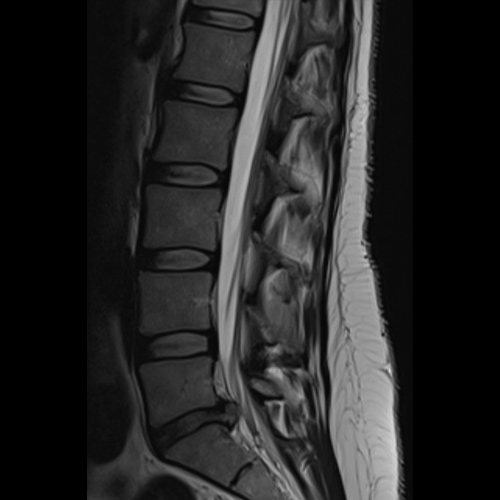

Spinal stenosis (Lumbar) Spinal stenosis (Cervical) Spinal stenosis (Thoracic) Lumbar Disc Herniation Spondylolisthesis Cervical Foraminal Stenosis Vertebroplasty Lumbar Fusion Anterior Cervical Fusion (ACDF) Posterior Cervical Fusion Thoracic Fusion Revision Lumbar Fusion Surgery Facet Joint Cyst Spinal Tumour Minimally Invasive Lumbar Fusion (XLIF) Minimally Invasive Lumbar Fusion (ALIF) Lumbar Fusion (TLIF) Thoraco-lumbar Fusion Lumbar Corpectomy Complex Lumbar Spine Surgery (Spino-pelvic fixation) Complex Cervical Spine Surgery Complex Thoracic Spine Surgery Occipito-cervical Fusion Minimally invasive surgery for thoracic disc herniation Other Related Topics